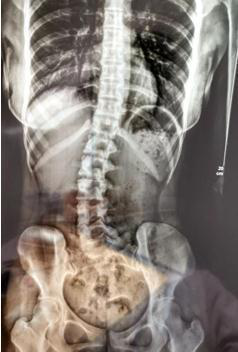

睡姿對脊柱側(cè)彎的影響

脊柱側(cè)彎的原因有很多,除了先天性原因和特定疾病之外,也由于不正確的姿勢引起的,睡眠姿勢也是其中重要的一部分。

睡姿不當(dāng),長時間側(cè)躺睡而且是側(cè)同一邊,并且下腿擺姿不正確。原有正常的脊柱體態(tài)在日積月累的錯誤睡姿中逐漸失衡,骨盆與脊柱位置變化。

在18歲以前,身體的可塑性較強(qiáng),通過持續(xù)的治療和科學(xué)的生活姿勢、運(yùn)動,是比較容易進(jìn)行矯正的。

對于脊柱側(cè)彎的患者,除了在醫(yī)院進(jìn)行規(guī)范治療外,更要糾正不良的生活習(xí)慣與運(yùn)動模式,保持良好的運(yùn)動習(xí)慣,在運(yùn)動方面,可進(jìn)行游泳、吊單杠,跑步等雙側(cè)平衡的運(yùn)動,少或者不要進(jìn)行羽毛球、乒乓球等單側(cè)運(yùn)動。